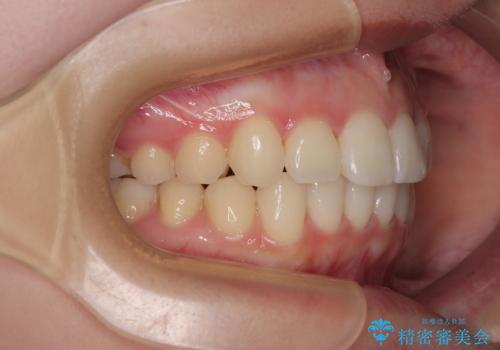

- 上下前歯のデコボコを気にして来院された患者様です。

ワイヤー矯正でもマウスピース矯正でも可能でしたが、短期間で、自身の手を煩わせることなく治療を行いたいとのことで、ワイヤー装置にて矯正治療を行うこととしました。

舌の突出癖により、出っ歯仕上がりとなる可能性がありましたが、舌のトレーニングを頑張っていただき、1年強で終えることができました。